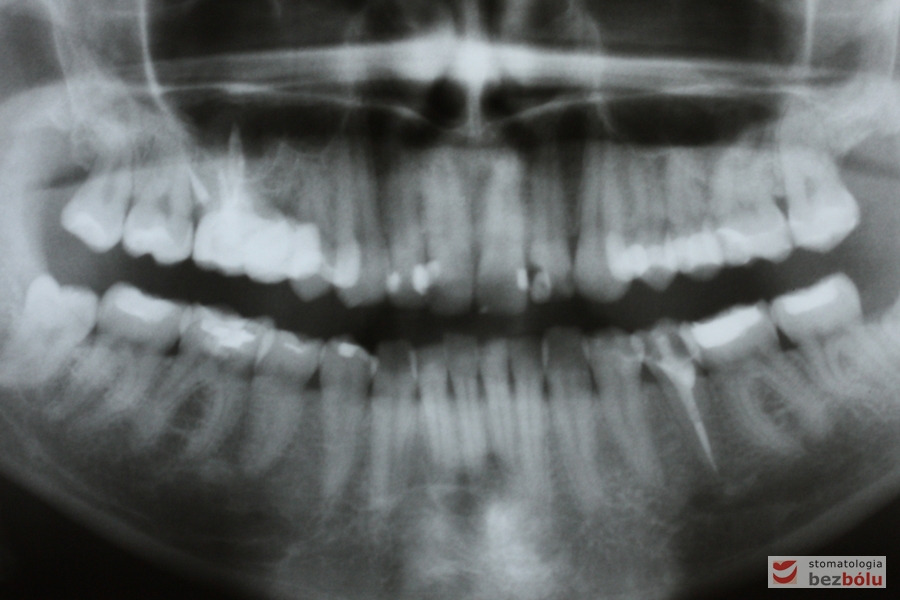

Kontrola radiologiczna - OPG

Kontrola radiologiczna – OPG

Pantomogram - kontrola radiologiczna zaraz po zdjęciu aparatu cienkołukowego

Pantomogram – kontrola radiologiczna zaraz po zdjęciu aparatu cienkołukowego